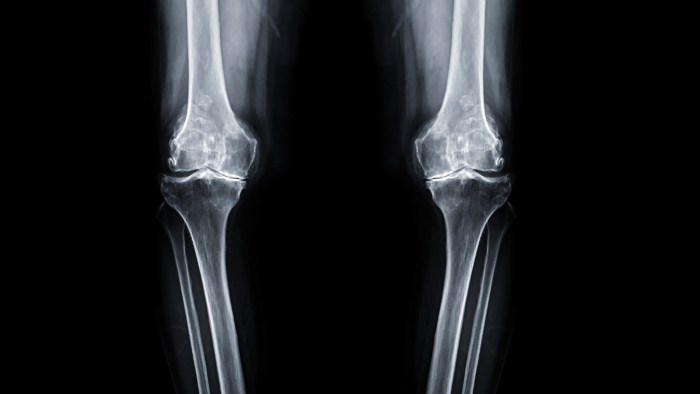

5. Reduced Joint Space

On X-rays, OA often shows up as narrowing of the joint space, a sign that the cartilage is essentially gone. (23) Less space means more stiffness and less freedom to move.

Symptoms of Osteoarthritis

x-ray of knees with osteoarthritis joint deformity

Not everyone experiences OA the same way, but common symptoms include (18, 24):

• Aching joint pain that worsens with activity

• Morning stiffness (usually lasting less than 30 minutes)

• Clicking, grinding, or popping sounds (crepitus)

• Swelling and tenderness

• Reduced range of motion

• Joint deformities in advanced stages

OA often affects weight-bearing joints like the knees, hips, and spine, as well as the hands. (25) And unlike rheumatoid arthritis (which we’ll get to next), OA tends to be asymmetrical, you might have it in one knee but not the other.